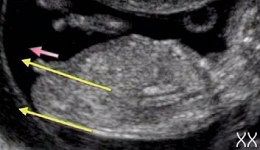

А вот фото, которые я нашла на просторах интернета с "инструкцией" на мальчика

у мальчика половой бугорок со спинкой образуют угол в 30 градусов

У девочек Угол со спинкой меньше 30 градусов

Все фото-примеры как раз рассказывают про определение пола на 13-ой недельке